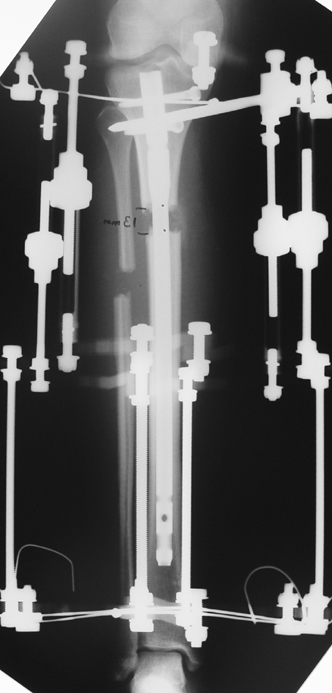

İntramedüller çivinin yerleştirilmesi ve osteotomi: Hasta traksiyon masasına supin pozisyonda yatırılır ve sağlam bacak altta olacak şekilde bacaklar makas pozisyonuna alınır. Standart yolla piriformis çukurundan medulla içine girilir ve kılavuz tel üzerinden kullanılacak çividen 1.5 mm daha kalın oyucu ile medulla oyulur. Proksimal femur, çivinin proksimali daha kalın olduğu için daha kalın oyulur. Radyografide osteotomi hattı planlaması yapılır. Planlama yapılırken uzatma sonunda distalde en az 8 cm. çivi kalması stabilizasyon için gereklidir. Kortikotomi perkütan olarak kortikotom ile tamamlanır. Daha sonra kılavuz tel çivinin boyunu ölçmek için distale ilerletilir. Uygun boyda intramedüller çivi çakılır. Son olarak çivi proksimalden kilitlenir ve bir adet dren konarak ameliyatın birinci kısmı tamamlanır.

Eksternal fiksatör uygulanımı: İntramedüller çiviye değmeden aşağıya ve yukarıya üçer adet Schanz vidası gönderilir. Vidalarla çivi arasında en az 1 mm den fazla mesafe olmalıdır.

Postoperatif Bakım: Distraksiyona (Kemik parçalarının arasının birbirinden uzaklaştırılması yöntemi) 10. günde başlanır. Günde 4 defa 6 saatte bir 0.25mm uzatma yapılır. Operasyondan 1-2 gün sonra kalça ve diz çevresi hareketlere başlanır. Alt ekstremite kısalıklarının tedavisi uzun yıllar boyunca hem hasta hem de cerrah için zorluklarla dolu olmuştur. İlizarov’un distraksiyon osteogenezisi kavramını tanımlamasından sonra geliştirilen teknikler bu konuda yeni bir çağın öncüleri olmuşlar ve daha önceki yıllarda görülen komplikasyonların oldukça azaldığı uygulamalar olarak anılmışlardır.

Biz son zamanlarda, seçilmiş vakalarda, uzatma sonrası uzunluğu ve “alignment’ı” korumak amacı ile unilateral dinamik aksiyel fiksatör ve kilitli intramedüller çivi kombinasyonunu tercih etmekteyiz. Bu yöntemin ön şartları medullanın en dar çapının 7 mm.’den geniş olması ve uzatma sonrası distalde en az 8 cm. uzunluğunda çivi kalabilmesidir. İntramedüller çivi hem uzatma esnasında femurun üzerine gelen makaslama ve bükülme kuvvetlerini nötralize etmekte hem eksternal fiksasyon süresini kısaltmakta, hem de yeni oluşan kemiği kırıklara karşı korumaktadır. Serimizde bir vakada subtrokanterik femoral osteotomi yapılmıştır. İntramedüller çiviye rağmen varus angulasyonu oluşması yönünde bir dezavantaj tespit etmedik.

İlizarov, distraksiyon osteogenezisi için endosteal kan dolaşımının önemini vurgulamıştır. Biz tüm vakalarımızda femuru oyarak intramedüller çiviyi çaktık; buna rağmen hiçbir vakada kallus oluşma süresi tahminimizden daha uzun olmadı. Bu yüzden medüller dolaşımın bozulmasına bağlı yeni kemik oluşma hızında bir yavaşlama olmadığını düşünüyoruz. Oyma sonrası meydana gelen revaskülarizasyon, intramedüller çivili fiksasyon stabilitesi ve erken fonksiyonel yüklenme bu gerçeğin temelini oluşturmaktadır. Eksternal ve internal fiksasyon yöntemlerinin kombine kullanımının potansiyel dezavantajları kan kaybının artması, intramedüller infeksiyon, yağ embolisi olasılığı ve aşırı metal yüküdür. Bunların içinde en çok korkulan problem bir çivi dibi infeksiyonun tetikleyeceği derin intramedüller infeksiyondur (panosteomyelit). Bizim serimizde bu yönde hiçbir komplikasyon gelişmemiştir. Bu olası komplikasyonun önlenmesi amacı ile uzatma sonundaki kilitleme medialden yapılmalıdır; ayrıca intramedüller çivi ve eksternal fiksasyon pinlerinin teması önlenmelidir.